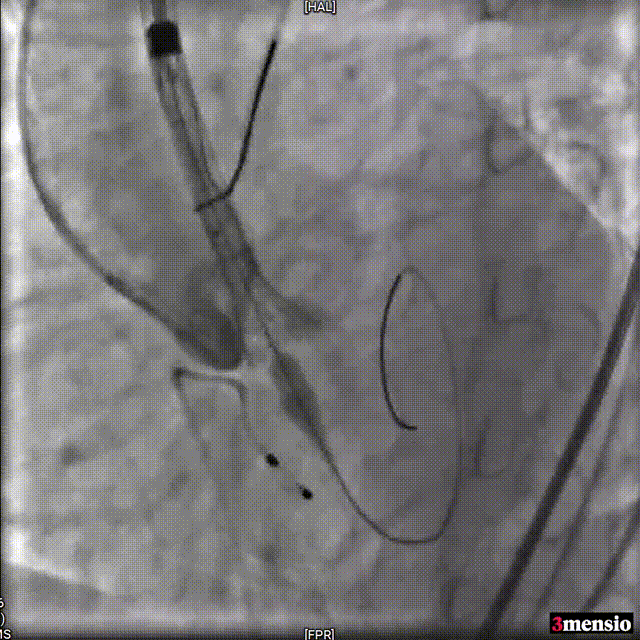

导丝跨瓣

23mm球囊预扩

Snare辅助输送系统过弓

瓣膜定位

释放瓣膜

瓣膜释放至工作位评估